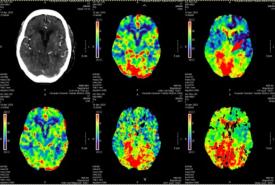

Defying All Odds: Successful Thrombolysis in a Nonagenarian with Posterior Circulation Infarct

Case Report 27 Jan, 2025